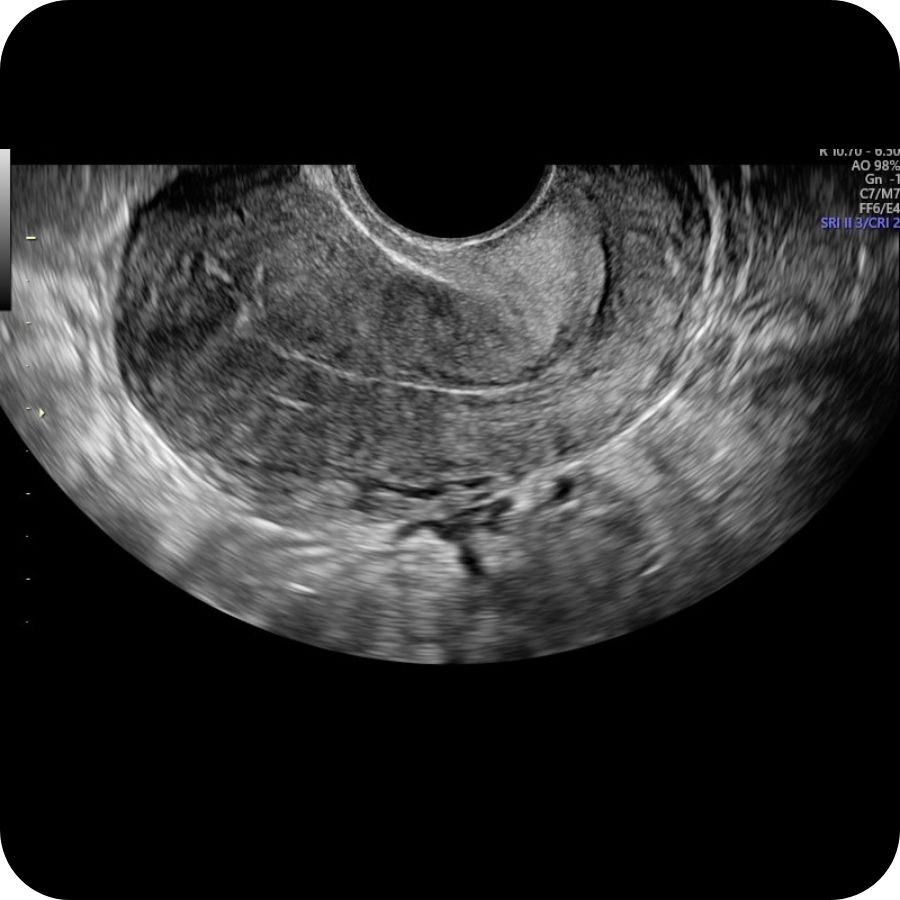

Early Pregnancy Scan (5-12 Weeks)

An early pregnancy scan is often one of the most reassuring steps in early pregnancy. At HerView, we understand that these first weeks can be both exciting and emotional, and many women simply want clarity, comfort, and a first connection with their growing baby. Our Early Pregnancy Scan, carried out…